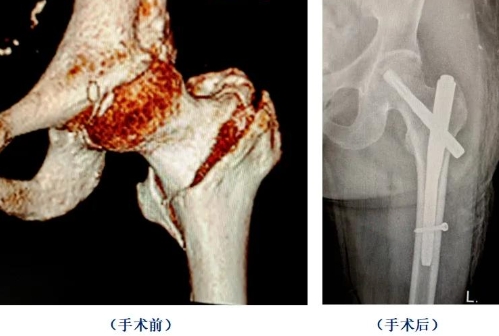

97岁的李女士因为意外摔倒导致左髋部疼痛难忍,不能站立,家人紧急拨打120送到集团本部急诊科就诊,结合髋部CT检查诊断为左股骨粗隆间粉碎性骨折。由于患者平时基础病情较多且重,经检查合并高血压、冠心病、糖尿病、肺部感染、I型呼吸衰竭等并发症,手术风险高。集团骨关节与创伤外科中心万修阳主任专家团队联合心内科、肺病科及麻醉手术科等多学科会诊,术前周密准备,为患者成功实施股骨近端交锁髓内钉内固定手术(PFNA)。

集团骨关节与创伤外科中心主任万修阳介绍,对于高龄老人股骨粗隆间骨折,集团采用闭合牵引复位,股骨近端交锁髓内钉内固定手术(PFNA及Intertan系统),具有创伤小、手术时间短、出血量少,术后恢复快等优点,是目前国内主流术式。三个手术切口长度分别为3厘米、2厘米、1厘米。手术不需要对骨折断端软组织及骨膜进行剥离,对骨折端周围血供破坏少,更利于骨折愈合。